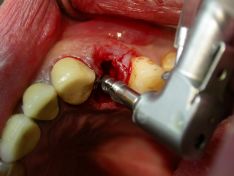

La procedura chirurgica preimplantare è stata eseguita con una fresa pilota di

ø 2,00 come prefresatura con tacche da 13 mm. di profondità, per creare una

strada piu’ palatale all’alveolo anatomico , e con frese intermedie di diametro

ø 2,50- 3,30 –3,75 - 4,25 mm. con tacche di riferimento da 13 mm. in altezza,

tutte in sequenza graduale crescente;

Frese chirurgiche calibrate ad irrigazione interna, con l'ausilio di un micromotore da Implantologia a basso regime di giri (375 rpm.) con un torque pari a 56 Newton ( forza su cm2) con utilizzo di acqua fisiologica (sodio cloruro 0,9%) raffreddata, per evitare surriscaldamento e necrosi ossea.